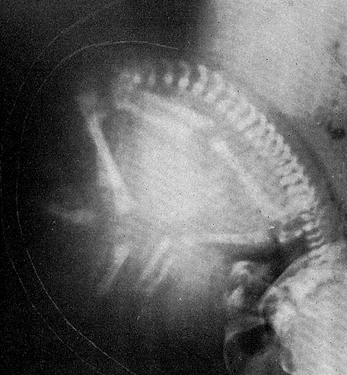

X-ray of a pregnant abdomen (1955)

Announced to the world in 1896, Wilhelm Röntgen’s X-rays were the most sensational invention in what has become the major field of medical imaging. By 1897, obstetricians had X-rayed the female pelvis. They saw foetal parts by the 12th week of pregnancy and constructed maps of the forming bones. In the mid-20th century, X-ray photographs such as this one in an American textbook were used to assess placental location, foetal position and presentation, and bone maturation, as well as the size of the pelvic outlet.

However, after Hiroshima and Nagasaki, the mutagenic effects of X-rays came under much closer scrutiny. The final blow was a 1956 study by an Oxford team led by epidemiologist Alice Stewart that found an increased incidence of childhood cancer following in utero irradiation – so by the mid-20th century, radiography of foetal development had been largely abandoned.